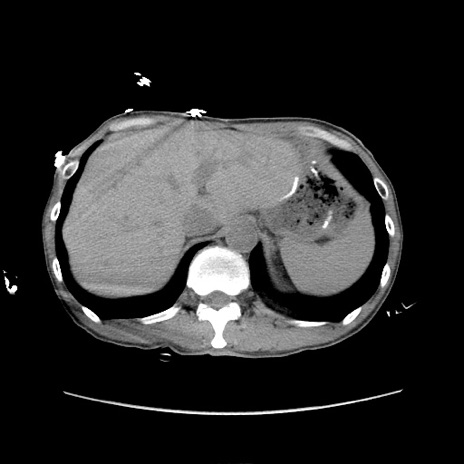

症例11(横断像)

【症例】 60歳代男性

【主訴】 下腹部痛

【現病歴】 本日夜中より下腹部痛の症状認め、受診。

【既往歴】 膀胱癌(膀胱全摘+尿管皮膚瘻術) 、胃癌術後

【身体所見】 BT 35.3℃、PR 58/min、BP 136/98mHg、腹部平坦、軟、腸蠕動音±、ストマ留置あり、左上腹部~正中部に圧痛あり、反跳痛なし。

【データ】WBC 5100、CRP0.01